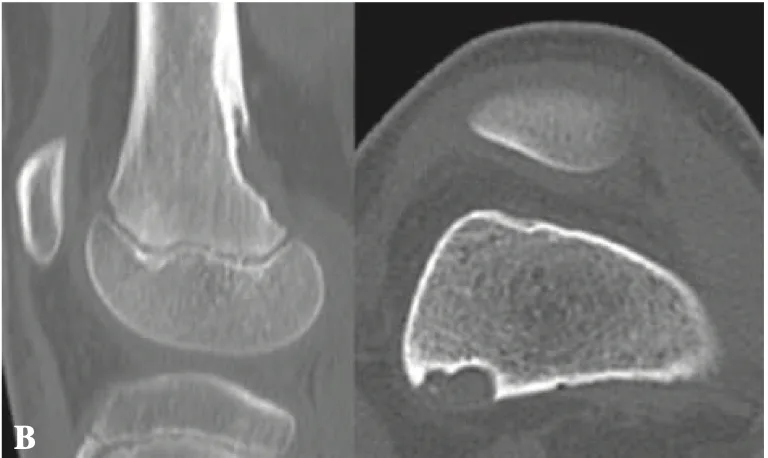

正面像(A)では, 大腿骨の内側部が透けるように写る病変が, 側面像(B)では, 骨が隆起するように写る病変がそれぞれ認められます.

引用元:Vieira RLR. MRI features of cortical desmoid in acute knee trauma. AJR Am J Roentgenol. 2011. 196.

X線写真を確認すると, 遠位大腿骨皮質骨不整 distal femoral cortical irregularity(以前は, 皮質デスモイドcortical dermoid, avulsive cortical irregularityなどと呼ばれていた)所見が疑われました.

大腿骨の後内側の皮質骨が凹むような病変が認められます.

引用元:Muramatsu K. Distal femoral cortical irregularity in children. Acta Orthop Belg. 2015. 81.

CTの結果, 大腿骨の後内側の皮質骨が凹むような所見を確認し, 診断が確定しました.

遠位大腿骨皮質骨不整は, 小児期から青年期にかけて見られる, 骨腫瘍と誤認されやすい良性・一過性の病変です.